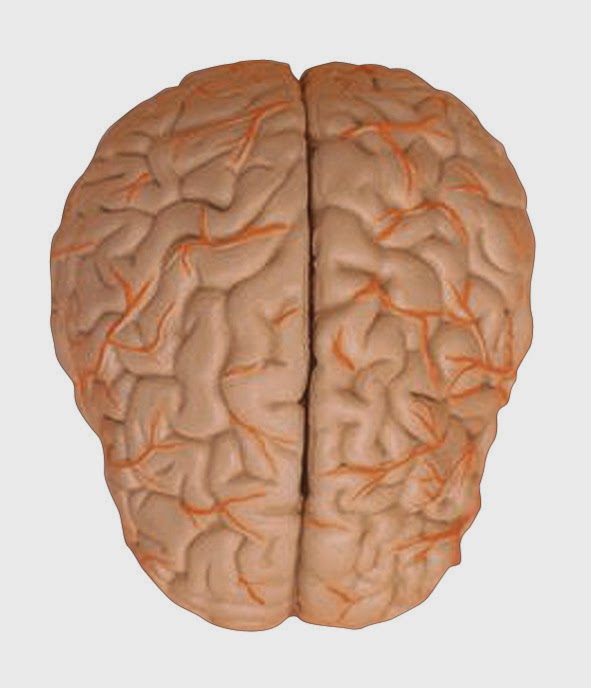

-Necesita un 20 % de la sangre y del oxígeno del cuerpo, ocupa aproximadamente 1 y 1,2 litros de sangre.

-El cerebro está compuesto en un 60% de grasa.

-Por su composición de tejidos grasos, vasos sanguíneos y el agua que guarda, su consistencia es parecida al tofu o la gelatina.